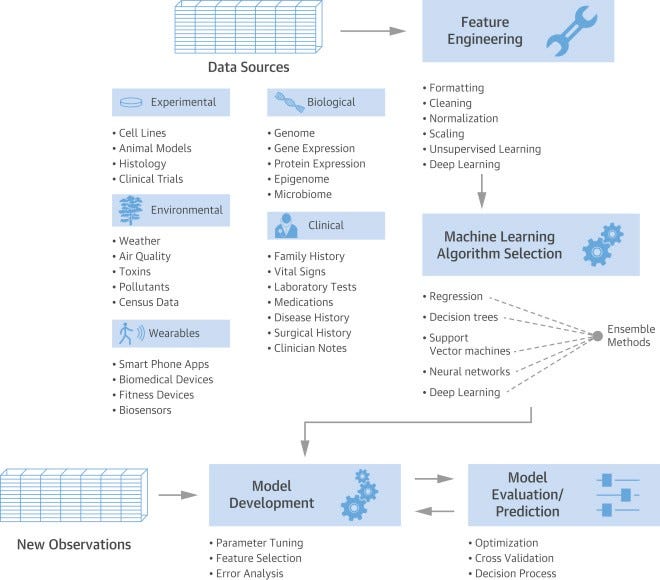

The central promise of machine learning is to incorporate data from a variety of sources (clinical measurements and observations, biological –omics, experimental results, environmental information, wearable devices) into sensible models for describing and predicting human disease. The typical machine learning workflow begins with data acquisition, proceeds to feature engineering and then to algorithm selection and model development, and finally results in model evaluation and application. Below figure provides the overview of a typical machine learning workflow in the healthcare industry (Johnson et al., 2018) -

机器学习的中心承诺是将来自各种来源(临床测量和观察,生物组学,实验结果,环境信息,可穿戴设备)的数据整合到用于描述和预测人类疾病的明智模型中。 典型的机器学习工作流程从数据采集开始,进行特征工程,然后进行算法选择和模型开发,最后导致模型评估和应用。 下图概述了医疗保健行业中典型的机器学习工作流程(Johnson等,2018)-